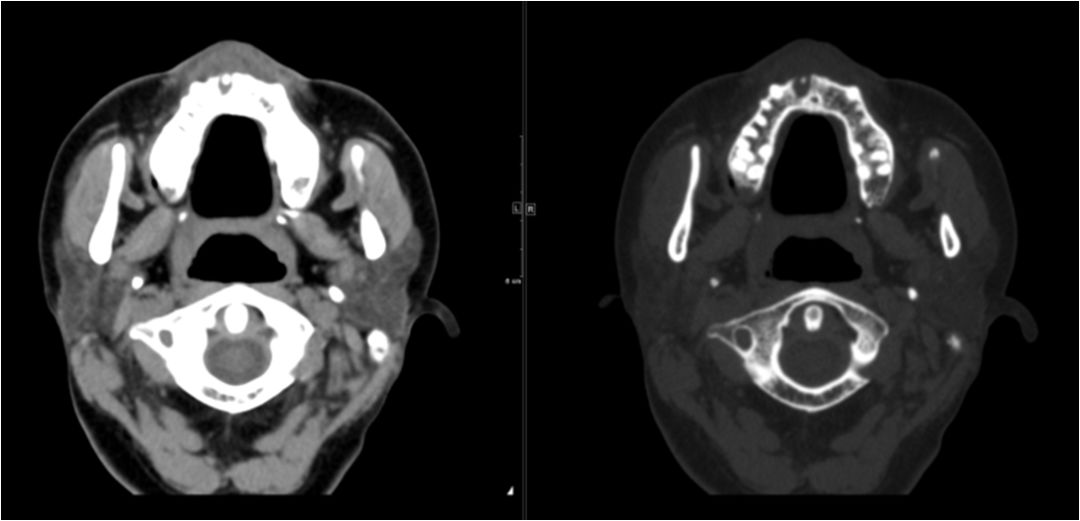

02 咀嚼肌间隙、翼下颌间隙、颊间隙

男,31岁,患者约3天前出现右侧面部口角区局限性肿胀,无明显触压痛,既往右侧下颌后牙区阵发性锐痛,曾自行口服消炎药处理,自诉牙痛症状无明显缓解,约3天前牙痛症状加重,伴夜间痛,后自觉右侧面部肿胀,约2天前开始发热,体温39.8℃。